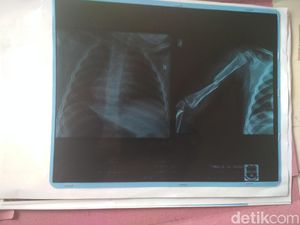

Seorang ayah pengangguran yang suka mengonsumsi sabu tega menempeleng anak bayinya yang baru berusia 6 hari. Bayi itu juga dibanting hingga mengalami memar.